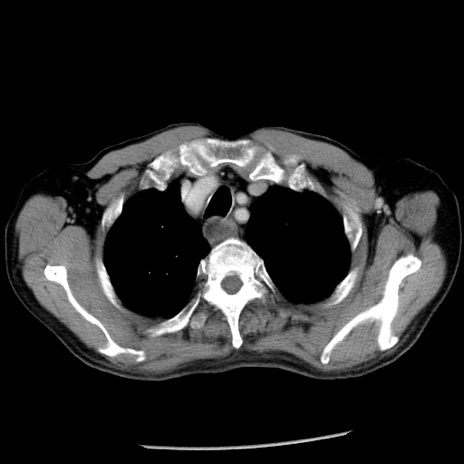

症例26(横断像)

【症例】80歳代男性

【主訴】嘔吐

【現病歴】昨晩2回嘔吐あり、今朝になっても嘔吐あり。来院。

【既往歴】胃潰瘍

【身体所見】意識清明、BT 37.6℃、BP 166/95mmHg、HR 100bpm、SpO2 97%、腹部:平坦・軟、腸蠕動音聴取良好、圧痛なし。

【データ】WBC 21900、CRP 1.46